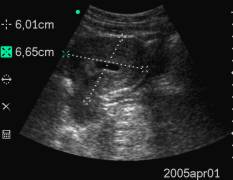

Data inserimento: 15 /07/2005Data esame: 28/06/2005 Strumento: Toshiba 380A Età paziente: F 40 anni Gravidanza alla V settimana di gestazione, documentata per via sovrapubica e per via transvaginale, con evidenza in ambedue le modalità della camera gestazionale. Elaborazione digitale: Andrea Dini